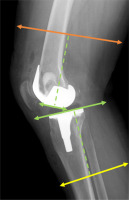

Fig. 2

Lateral view of lower limb measurement areas. The green dashed line marks a distance of 10 cm from the intercondylar line and the tibial plateau, marking the femoral and lower leg measurement regions indicated by the orange and yellow lines, respectively.